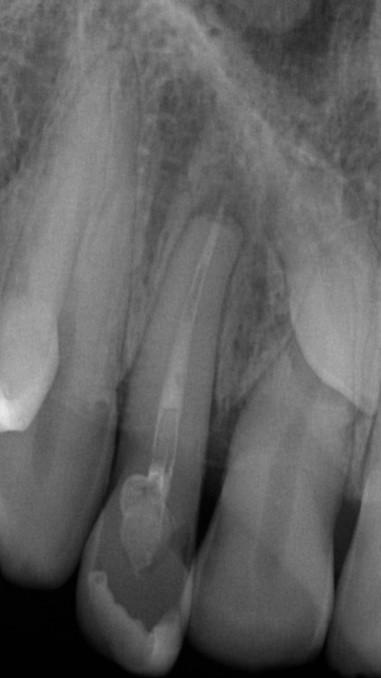

A 10 éves férfi páciens a felső frontfogai késői/nem megvalósuló előtörése miatt kereste fel a rendelőnket. A klinikai és a radiológiai vizsgálat során a jobb felső nagymetszőfog impakcióját észleltük (1. ábra). A fog horizontális tengelyállással és dilacerált gyökérrel rendelkezett. A felső dentális középvonal a fogak vándorlása miatt jelentős mértékben elcsúszott. A bal felső kismetszőfog is rendkívül kedvezőtlen pozícióba került.

Dr. Kazem Dalaie, dr. Samin Ghaffari, dr. Mazir Mir (Irán, Németország) 1. a ábra: Az intraorális felvételen jól látható a jobb felső nagymetszőfog lehetséges impakciójára utaló foghiány.

1. b ábra: A panoráma röntgenfelvételen megfigyelhető a teljes impakcióban lévő jobb felső nagymetszőfog. 1. c ábra: A CBCT felvétel is igazolja a jobb felső nagymetszőfog impakcióját.

sok korrigálása, valamint az impaktálódott fog előtöréséhez szükséges hely megteremtését követően, egy merev acél ív segítségével stabilizáltuk a fogakat. Ezt követően elvégeztük a jobb felső nagymetszőfog sebészi feltárását. A fog koronáját csupán lágyrész borította, ezért nem volt szükség a csontállomány elvételére. A felszabadítás során egy 975

nm-es hullámhosszon pulzáló üzemmódban alkalmazott lézert használtunk (LaserHF standard, Hager & Werken). A teljesítménye 3 W, az aktív ciklus-idő 50%-os, a vezetőszál átmérője pedig 0,4 mm volt (2. ábra). A lézert 150 másodpercen keresztül alkalmaztuk. A fogat borító lágyrészek eltávolítását követően egy láncos brekettet rögzítettünk a metszőfog bukkális felszínére. A műtétet követően nem tapasztaltunk vérzést, nem alakult ki oedema, valamint a páciens sem számolt be fájdalom vagy bármely egyéb kellemetlenség fennállásáról. A felszabadítást követően a páciens minden hónapban háromszor jelent meg a felszabadított területre ránövő lágyrészek és az íny lézeres eltávolítása céljából. A beavatkozások során ugyanazt a lézer készüléket használtuk, mint amivel a felszabadítást végeztük. Közvetlenül a felszabadítást követően megkezdtük a fog finom extrudálását a láncos breketthez kötött füzérgumi segítségével.

2. ábra: Az impaktált fog lézerrel asszisztált sebészi feltárása. 3. ábra: A kezelés megkezdését követő 15. hónapban megfigyelhető a sikeres felszabadítást, fogmozgatást és pozicionálást követően látható állapot.

A 975 nm-es hullámhosszt elsősorban sebészi beavatkozások végzése során alkalmazzák. Az ezzel a hullámhosszúsággal rendelkező lézersugarak csak kis mélységben képesek a lágyrészeket penetrálni, valamint hagyományosan nem ezeket szokták biostimuláció során használni. Ugyanakkor minden sebészi célra alkalmazott lézer körül megfigyelhetünk egy csökkenő intenzitással (azaz fényerővel) rendelkező gyűrűt, amely perifériáján biostimulációs hatások is létrejöhetnek. Az alacsony energiájú lézeres terápia (low-level laser therapy; LLLT) során a lézeres fejet a lágyszövetektől nagyobb

távolságban vezetve, az alábbi paraméterek mellett alkalmaztuk: pulzus üzemmód, 100 mW teljesítmény, 660 nm-es hullámhossz. A lézeres fejen lévő nyílás nagysága 0,125 mm2 volt (0,4 mm átmérő). A biostimuláció során egy megközelítőleg 7 cm2-es területet világítottunk meg a kérdéses fog vesztibuláris és palatinális oldalának megfelelően. A megvilágítás időtartama minden találkozó során 150 másodperc volt. A leadott energia 15 J, az energiasűrűség pedig 17J/ cm2 körül mozgott. A lézeres terápiát a kívánt fogpozíció eléréséig minden hónapban megismételtük. Ez a folyamat

4. a ábra: A CBCT felvétel igazolja, hogy a jobb felső nagymetszőfog megfelelő pozícióba került. Az ínyszél lefutása kedvező, a fog gyökere körül elfogadható mennyiségű csontállomány ábrázolódik, valamint a gyökérfelszívódás mértéke sem túl kifejezett.

6 hónapon keresztül tartott. Ennek megfelelően a fog körül található szövetek a felszabadítás, valamint a havi kontrollok során 975 nm-es (több mint 25 J/cm2 energiasűrűség) és 660 nm-es hullámhosszúságú (12–18 J/cm2 energiasűrűség) lézersugarakkal is megvilágításra kerültek. Az impaktálódott fogat megközelítőleg 7 hónap alatt tudtuk megfelelő pozícióba mozgatni (3. ábra). Az orthodoncia kezelés aktív szakasza 18 hónapon keresztül tartott. A fogívek végső nivellálását és a fogak végleges pozícióba rendezését 0.018 × 0.025-ös acélívekkel végeztük.

A kezelés befejezésekor a páciens mosolya drámai mértékben javult, továbbá a frontfogak elhelyezkedése és az ínyszél lefutása is szemmel látható módon kedvezőbbé vált (4. ábra). A kezelés végén készült CBCT felvétel nem mutatta

csontfelszívódás jelenlétét, és csupán minimális mértékű gyökérfelszívódás bekövetkezését igazolta.

4. b ábra: A panoráma röntgenfelvétel is alátámasztja a CBCT felvételen látottakat. 4. c ábra: Az intraorális felvételen megfelelő fogpozíciók és kedvező ínyszéli lefutás ábrázolódik.

A lézerrel asszisztált felszabadítás előtt készített felvétel.

periapikális felvétel.

felvétel.

5. a ábra: 5. b ábra: A végső állapotról készült 5. c ábra: A végső állapotról készült